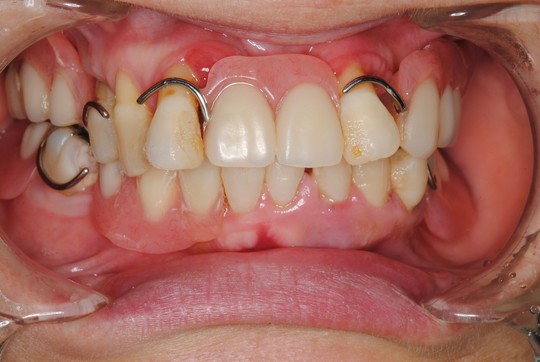

アタッチメント義歯(下顎義歯)

治療前

浮いたり外れたりしない下の入れ歯を製作して欲しいとのことで来院されました。